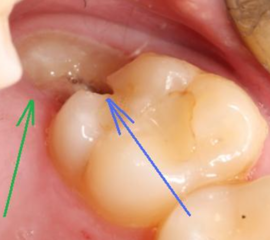

Неполное прорезывание приводит к формированию десневого капюшона – складки десны над зубом. Особенностью этого образования является то, что в него часто набивается пища, которую очень сложно вычистить зубной щеткой.

При обсеменении остатков пищи микроорганизмами развивается очень неприятное заболевание – перикоронарит.

- Иногда прорезывающийся зуб накрывает своеобразный «капюшон» из разросшейся слизистой. Под ним скапливаются остатки пищи и размножаются бактерии.

Этот процесс приводит не только к болезненности и отеку. Появляется неприятный запах изо рта и затруднение при глотании.

После еды там скапливаются остатки пищи, а при обычных гигиенических процедурах удалить их оттуда очень сложно. Поэтому в этом кармане развиваются бактерии, вызывающие воспалительный процесс.

У некоторых людей он протекает почти безболезненно и проходит сам. Но довольно часто появляются различные осложнения. Во время жевания десна может повредиться, бактерии проникают в ранку, и воспаление переходит в перикоронарит.

- Вздутие десны в виде «капюшона» над еще непрорезавшимся зубом. Если процесс роста затягивается, развивается воспаление мягких тканей после проникновения бактерий под «капюшон».